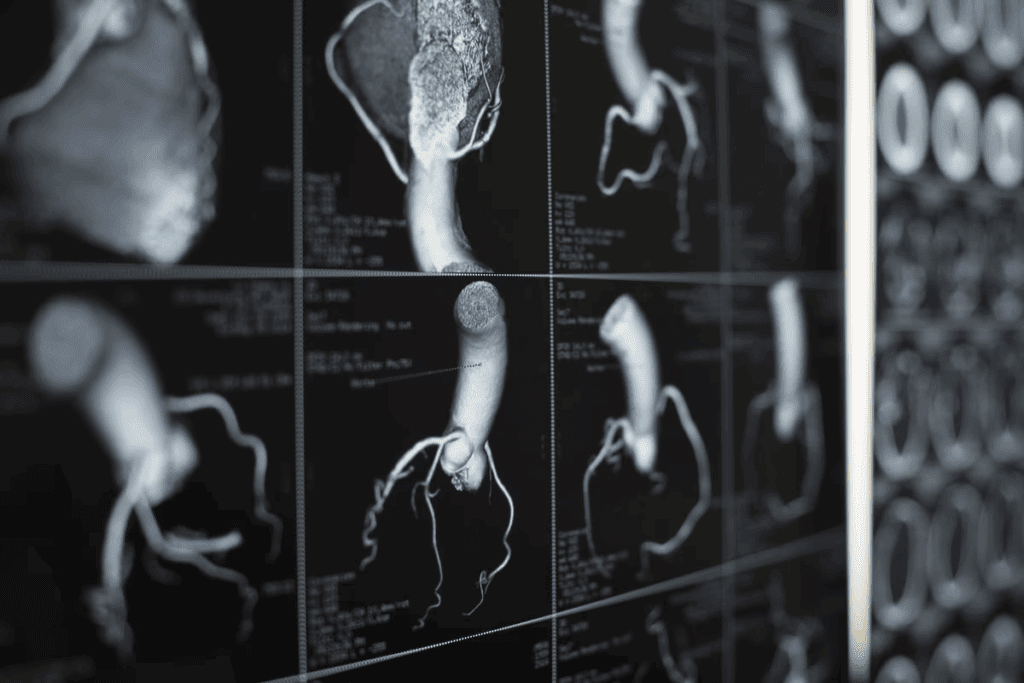

ACS happens when blood flow to the heart suddenly drops. This can cause heart attacks and unstable angina. The main reason is when a plaque in a heart artery bursts, causing a blood clot.

Coronary artery disease (CAD) is the main cause of ACS. CAD makes heart arteries narrow or block. This happens when plaque, made of fat and cholesterol, builds up and ruptures.

High LDL cholesterol can lead to atherosclerotic plaques in coronary arteries. These plaques can rupture, causing a blood clot. This can block the artery and lead to ACS.

The buildup of lipids in arteries makes them more likely to rupture. So, managing lipid levels is key to preventing ACS.